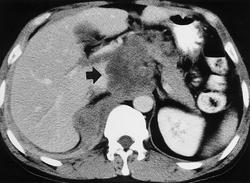

1) мезотелиома плевры и брюшины;

Злокачественная мезотелиома.

К осложнениям асбестоза относят рак легких. Сочетание асбестоза с раком легких и плевры встречается значительно чаще, чем с другими пневмокониозами, главным образом у мужчин. Рак легких в большинстве случаев развивается через 20-50 лет после начала работы в контакте с асбестовой пылью. Описаны случаи развития рака легких при стаже работы с асбестом менее 10 лет. Опухоли обычно локализуются в нижних долях легких. Механизм развития рака легких при асбестозе еще мало изучен. Считают, что иглообразные частицы асбестовой пыли, травмируя слизистую оболочку бронхов, вызывают ее гипер- и метаплазию, в дальнейшем происходит атипическое разрастание эпителия. Существует также мнение, что возникновению рака легких при асбестозе способствуют образующиеся у больных тяжелые бронхоэктатические изменения.